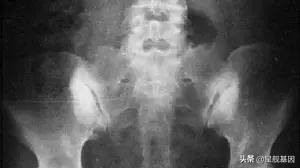

耻骨联合分离是指,骨盆前方两侧耻骨纤维软骨联合处分离。距离增宽成为耻骨分离;上下错动成为耻骨交错。

正常人耻骨间隙约4~5mm,没有上下错位的现象。为了更顺利的生出宝宝,准妈妈耻骨联合处会生理性增宽,当耻骨联合距离增宽超过10mm或上下错动而出现局部疼痛和下肢抬举困难等功能障碍,就是耻骨联合分离了。

最常见也明显的症状就是孕期和产后的鸭子步、外八字、排尿困难或尿*禁失**等等。很多妈妈常常因为耻骨联合分离痛到迈不开腿、痛到站不起来、痛到下不了床,丝毫不夸张。